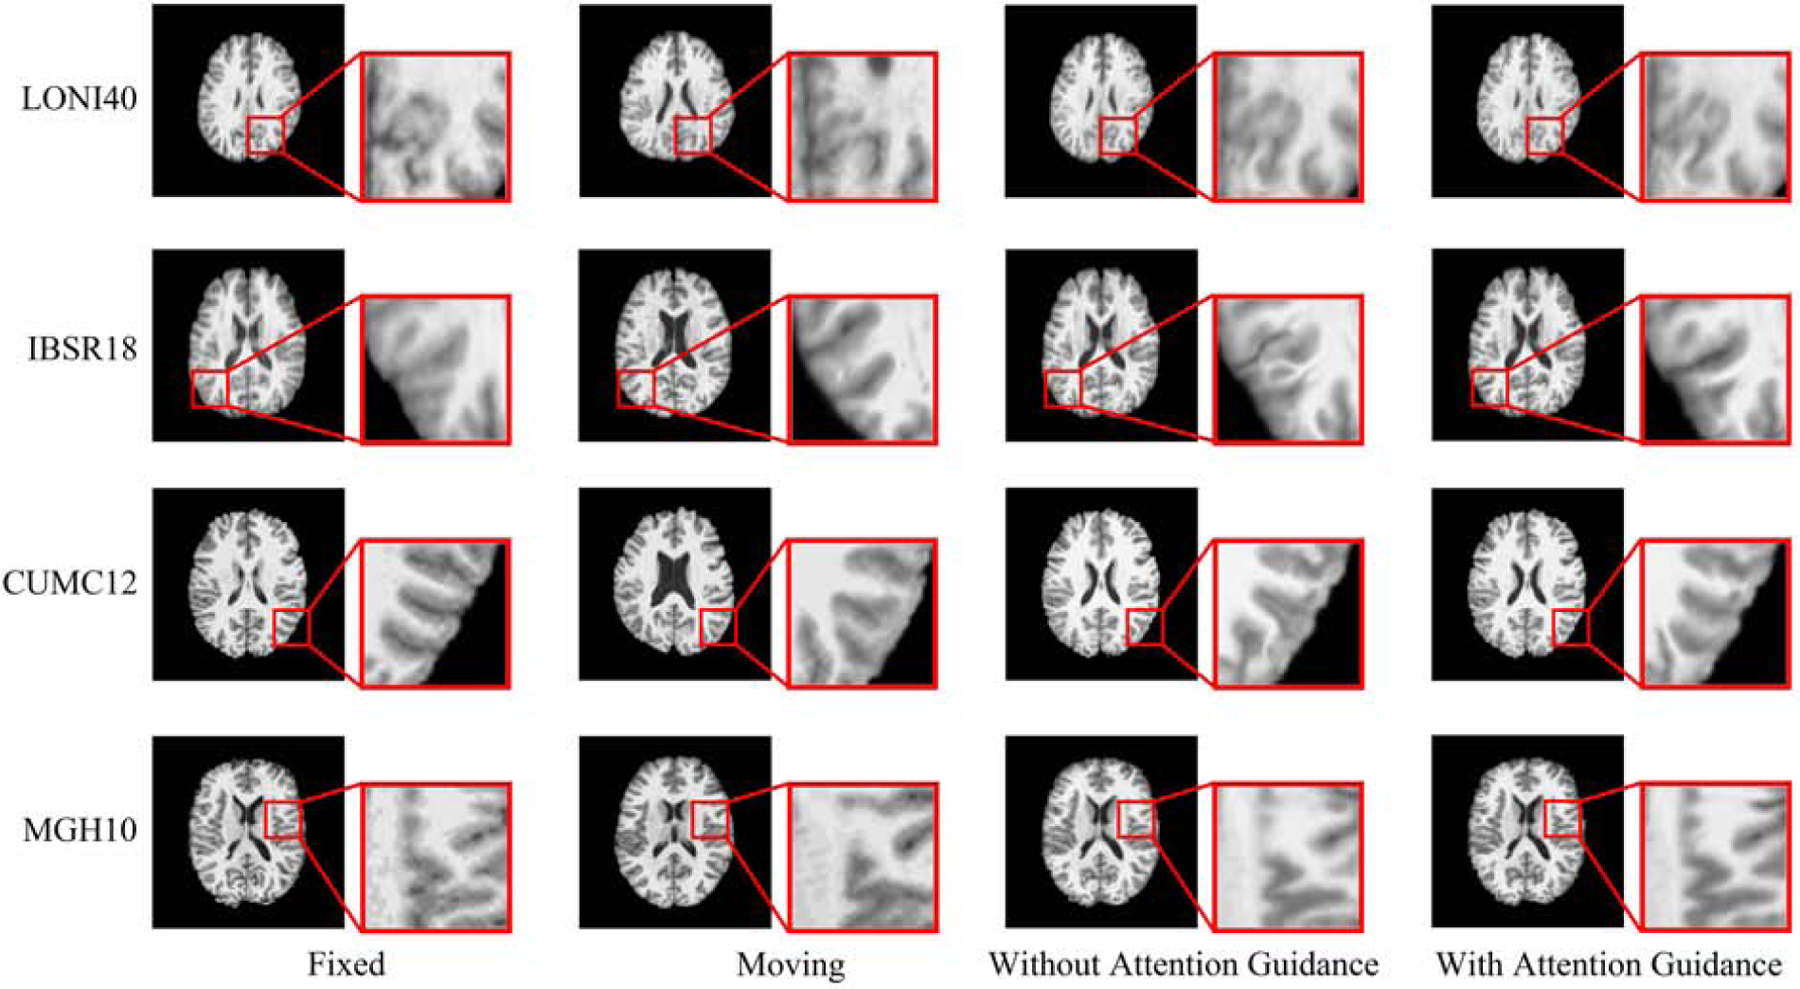

Table 4 summarizes the results for both configurations with and without attention guidance using the validation and testing datasets. The absence of the attention module results in lower DSCs, higher HDs, and greater deformation irregularity. Fig. 10 confirms the improvements given by attention guidance. This shows that the skip connection in the typical U-Net architecture is less effective in feature aggregation, compared with our attention guidance module, which allows adaptive learning of the features for the different layers in the decode path.

Table 4:

With and without attention guidance.

| Without Attention Guidance | With Attention Guidance | |||||||

|---|---|---|---|---|---|---|---|---|

| DSC (%) | HD (mm) | NJD (%) | NGJD (10−2) | DSC(%) | HD (mm) | NJD (%) | NGJD (10−2) | |

| LONI40 | 71.9 (±1.7) | 5.8 (±0.5) | 2.1 (±0.3) | 7.8 (±0.3) | 73.4 (±1.7) | 5.6 (±0.4) | 1.8 (±0.3) | 6.1 (±0.3) |

| IBSR18 | 55.8 (±3.2) | 8.0 (±1.0) | 6.6 (±1.7) | 10.2 (±0.4) | 58.4 (±3.1) | 7.6 (±0.9) | 4.6 (±0.1) | 9.0 (±0.6) |

| CUMC12 | 65.0 (±1.8) | 7.4 (±1.0) | 7.3 (±1.7) | 9.1 (±0.3) | 67.0 (±1.9) | 7.3 (±1.0) | 4.9 (±0.7) | 8.5 (±0.3) |

| MGH10 | 64.4 (±2.6) | 7.7 (±0.9) | 6.3 (±0.8) | 10.4 (±0.4) | 66.1 (±2.5) | 7.4 (±0.9) | 5.5 (±0.7) | 8.2 (±0.4) |

Fig. 10:

Example registration results with and without attention guidance.